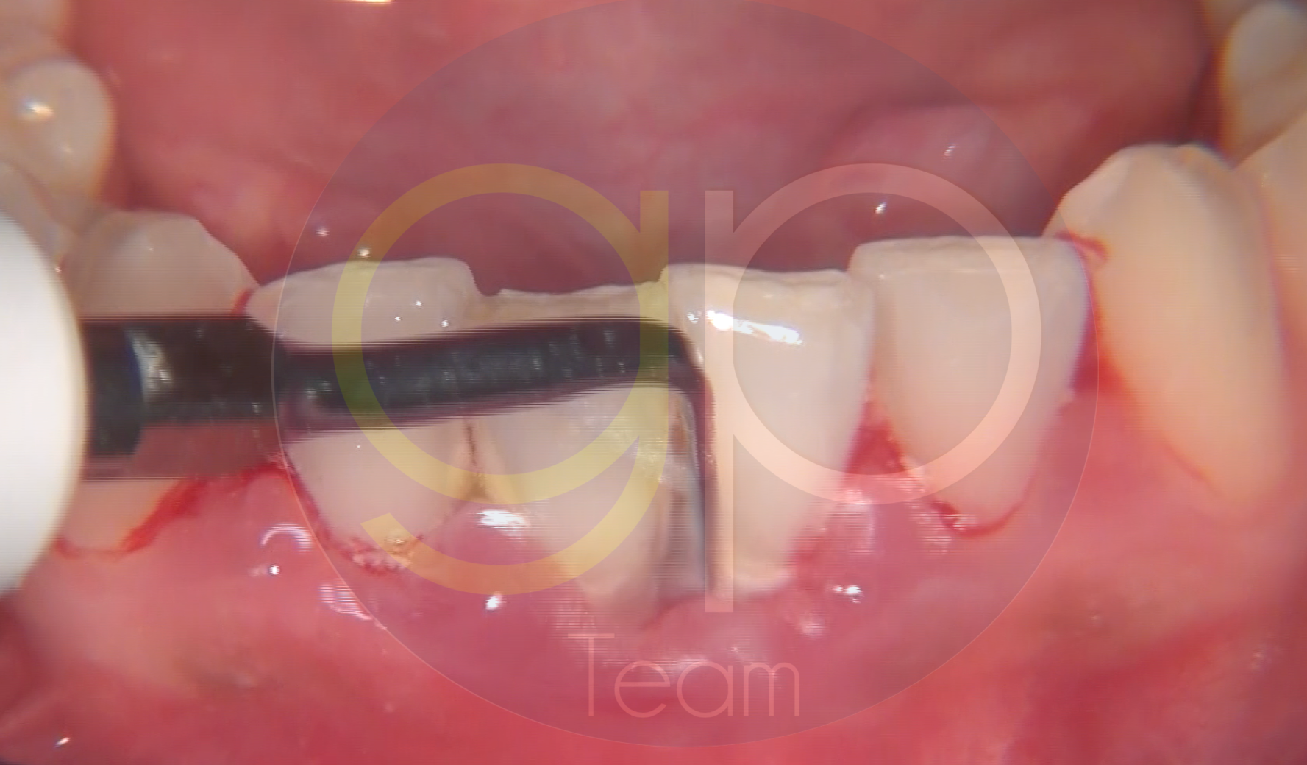

FIG. 1: Baseline. Paziente donna, con parodontite di Stadio III Grado C.

FIG. 2: Decontaminazione sopragengivale dei tessuti duri e molli, attraverso l'utilizzo del manipolo air polishing con la polvere Flash Perl.

FIG. 3: Strumentazione sopra e sottogengivale con l'ausilio della punta

G16, ideale per trattare i siti frontali e con morfologia stretta di pazienti con fenotipo gengivale sottile.